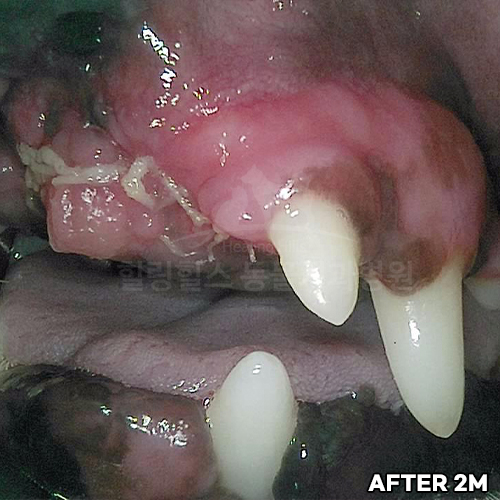

[최소침습적 발치 후 2주 경과]

샘플